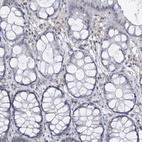

Immunohistochemical staining of human testis shows strong cytoplasmic positivity in cells in seminiferous ducts.